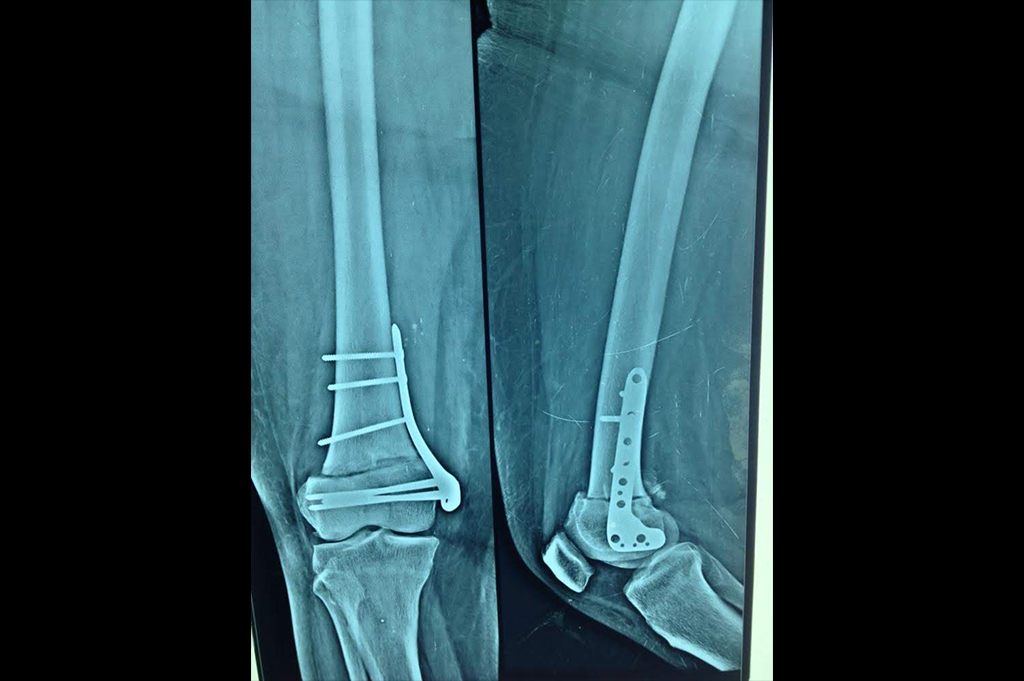

Distal Femur

Proximal Tibia